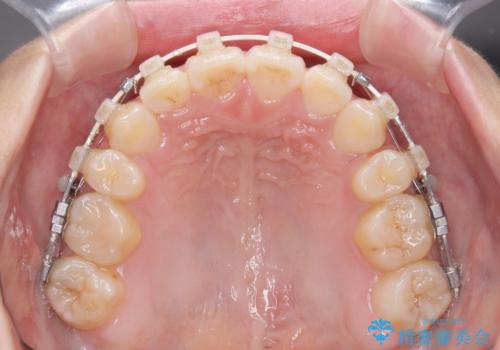

- 矯正装置

- 審美装置

- 1年6ヶ月

上下左右の第一小臼歯4本を抜歯し、ワイヤー装置にて矯正治療を行うこととしました。

舌のトレーニングをしっかりと行ってくださり、1年半という非常に短い期間で仕上げることができました。